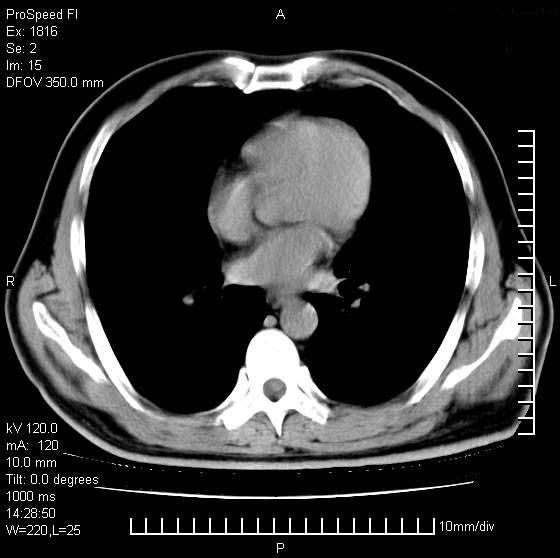

洞壁较厚内壁比较光整,两个病灶有关联性,纵隔淋巴结不大,考虑结核性空洞。

右肺上叶为两个病灶,前面为陈旧型结核灶,其后方病灶像肺脓肿

同意空洞型结核诊断,不过要注意随访复查。或与旧片比较。

内壁光滑,周围有卫星灶,还是结核可能性大,但壁太厚,应密切观察随访复查

考虑结核空洞可能性大,肺癌不能排除.